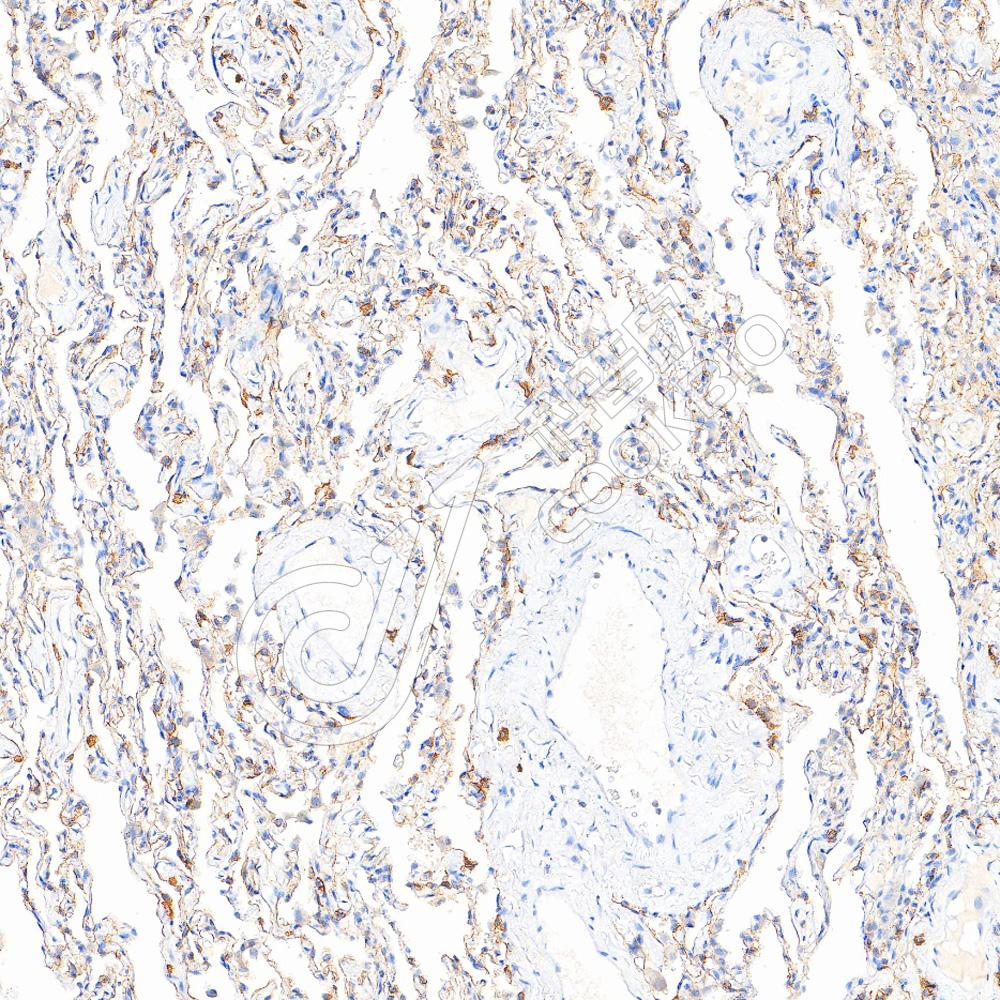

IHC检测CD4蛋白(货号 K5450186).

样品: 人结肠癌, 4%多聚甲醛 (货号KSG1101) 固定12-24小时.

抗原修复: 柠檬酸抗原修复液(干粉, pH 6.0) (KSG1201), 高压锅均匀喷气计时2分钟.

—抗: 1: 3500稀释, 4℃ 孵育过夜.

二抗: S-vision免疫组化多聚二抗(山羊抗兔),即用型 (货号KB3906), 室温孵育20分钟.

样品: 人扁桃体, 4%多聚甲醛 (货号KSG1101) 固定12-24小时.